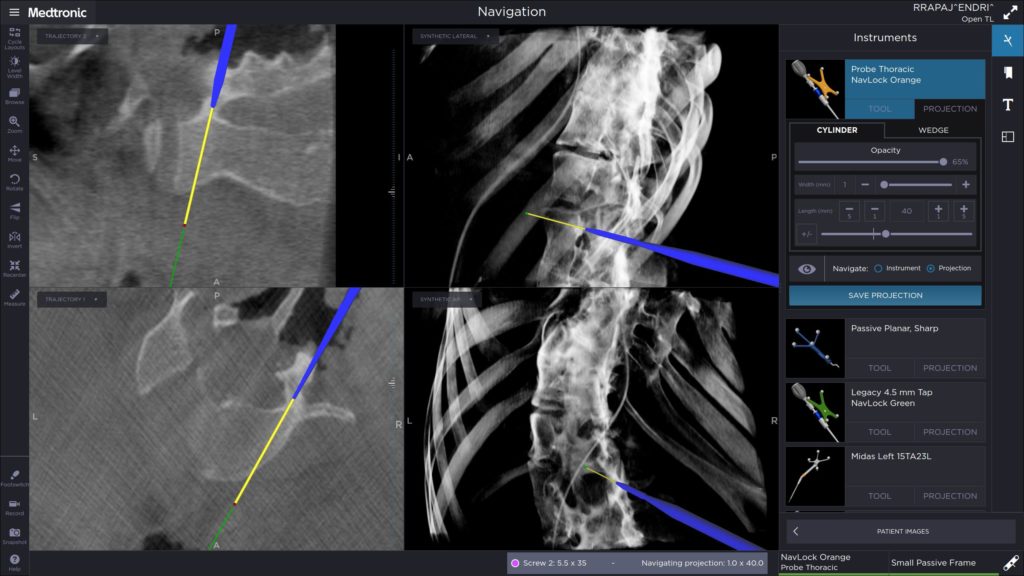

Η προσπέλαση ήταν οπίσθια στη Σπονδυλική Στήλη υπό συνεχή νευροπαρακολούθηση, χρησιμοποιώντας το ακτινολογικό σύστημα πλοήγησης (Navigation System) O-ARM. Το σύστημα αυτό βοήθησε εξαιρετικά στη τοποθέτηση των διαυχενικών κοχλιών του συστήματος σπονδυλοδεσίας και στη διενέργεια της οστεοτομίας.

Εικόνα 6

Διεγχειρητική εικόνα τοποθέτησης των διαυχενικών κοχλιών με την καθοδήγηση από το σύστημα O-Arm. Παρατηρούνται οι συγγενείς σπονδυλικές ανωμαλίες.

6. Στους υπόλοιπους, εκεί που κατορθώθηκε με τη καθοδήγηση του O-ARM να τοποθετηθούν κοχλίες, αυτοί είχαν πολύ μικρές διαμέτρους (3,5-4,5 χιλιοστά) και μικρά μήκη επίσης περί τα 35 χιλιοστά, λόγω των μικρών διαστάσεων των σπονδυλικών σωμάτων και των τόξων .

Εικόνα 19 : Διεγχειρητικές φωτογραφίες που έχουν ληφθεί από την οθόνη προβολής των εικόνων κατά την τοποθέτηση των κοχλιών με τη καθοδήγηση από το σύστημα πλοήγησης O-ARM.

Παρατηρούνται οι πολύ μικρές διαστάσεις των σπονδυλικών σωμάτων των μίσχων (pedicles) και των διαυχενικών κοχλιών.